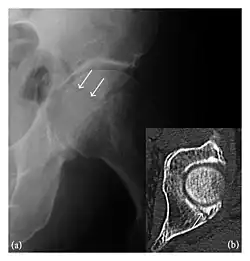

Occult osseous injuries may result from a direct blow to the bone by compressive forces of adjacent bones against one another or by traction forces during an avulsion injury. Lesions in the tibial plateau, hip, ankle, and wrist are often missed. In a tibial plateau fracture, any disruption of the posterior and anterior cortical rims of the plateau should be sought. Impaction of subchondral bone will appear as an increased sclerosis of the subchondral bone (Figure 1). In the hip, posterior acetabular fractures also present subtle radiographic findings. The acetabular lines should then be carefully examined keeping in mind that the posterior rim, which is harder to see on X-rays, is more frequently fractured than the anterior rim (Figure 2). In the wrist, detection of carpal bone fractures is often challenging, with up to 18% of scaphoid fractures radiographically occult. Carpal fractures, especially the scaphoid, are associated with the risk of avascular necrosis. In apparently normal wrist radiographs from symptomatic patients, if there is history of a fall on an outstretched hand with pain in the anatomic snuffbox, suggesting scaphoid injury, the initial examination with posteroanterior, lateral, and pronation oblique views must be complemented by other specific views such as supination oblique and the "scaphoid" view A careful examination of cortices for evidence of discontinuity or offset and cancellous bone for lucency is necessary (Figure 3).[1]

Figure 4: Dorsal triquetral fracture of the left wrist in a 30-year-old man after a trauma. (a) Anteroposterior radiograph shows a normal appearance. (b) Lateral radiograph of the same wrist demonstrates a chip fracture off the dorsal aspect of the triquetrum (arrow).[1]

Triquetral fracture usually occurs on the dorsal aspect by impingement from the ulnar styloid or avulsion of strong ligamentous attachment. The dorsal avulsion fracture or "chip fracture" appears as a small bony fragment on the dorsal aspect of the triquetrum and is best detected on the lateral view(Figure 4). When radiography is negative in patients with high suspicion of a fracture, both MRI and MDCT will be of value. However, it has been shown that MRI is superior for detecting trabecular fractures in carpal bones.